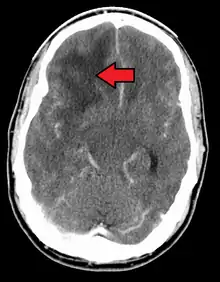

.jpg.webp)

When viewed with MRI, glioblastomas often appear as ring-enhancing lesions. The appearance is not specific, however, as other lesions such as abscess, metastasis, tumefactive multiple sclerosis, and other entities may have a similar appearance.[42] Definitive diagnosis of a suspected GBM on CT or MRI requires a stereotactic biopsy or a craniotomy with tumor resection and pathologic confirmation. Because the tumor grade is based upon the most malignant portion of the tumor, biopsy or subtotal tumor resection can result in undergrading of the lesion. Imaging of tumor blood flow using perfusion MRI and measuring tumor metabolite concentration with MR spectroscopy may add diagnostic value to standard MRI in select cases by showing increased relative cerebral blood volume and increased choline peak, respectively, but pathology remains the gold standard for diagnosis and molecular characterization.